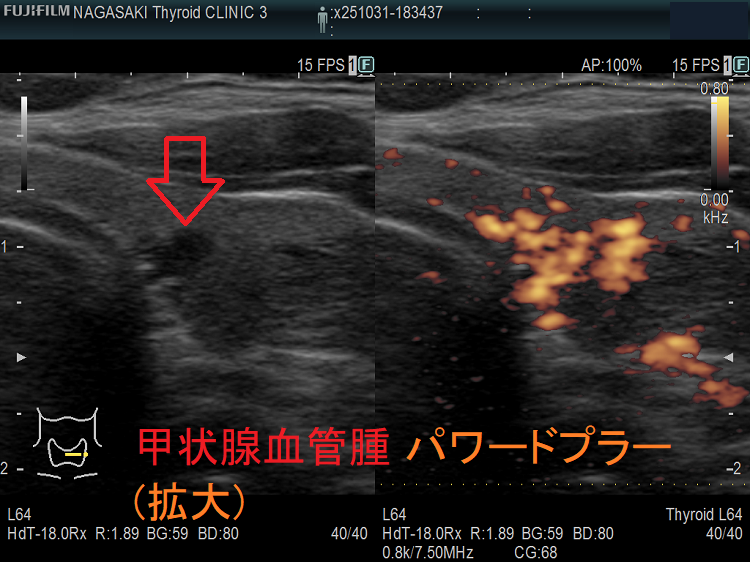

甲状腺に発生する血管腫は非常に稀で、日本の報告例もわずかです(日臨外会誌 72(3),579―583,2011)。

ケース①

ケース②

ケース③

甲状腺血管腫(拡大) ドプラーモード(eFlow);腫瘍内血管が3次元的に見え、毛玉の様。

ケース④

ケース⑤